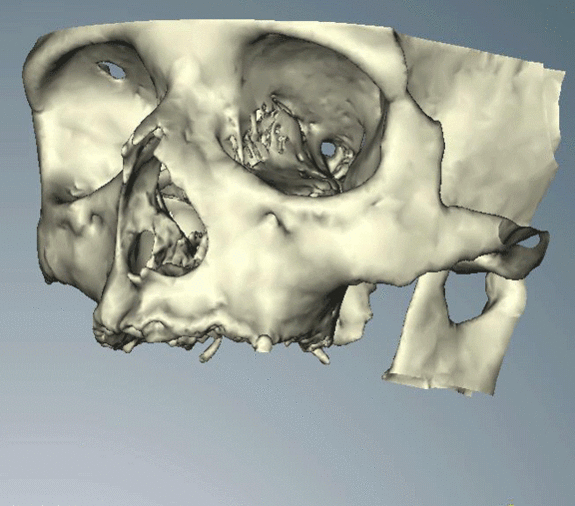

При планировании зубных имплантатов основное внимание уделяется общему состоянию здоровья пациента, местному состоянию здоровья слизистых оболочек и челюстей, а также форме, размеру и положению костей челюстей, соседних и противолежащих зубов.